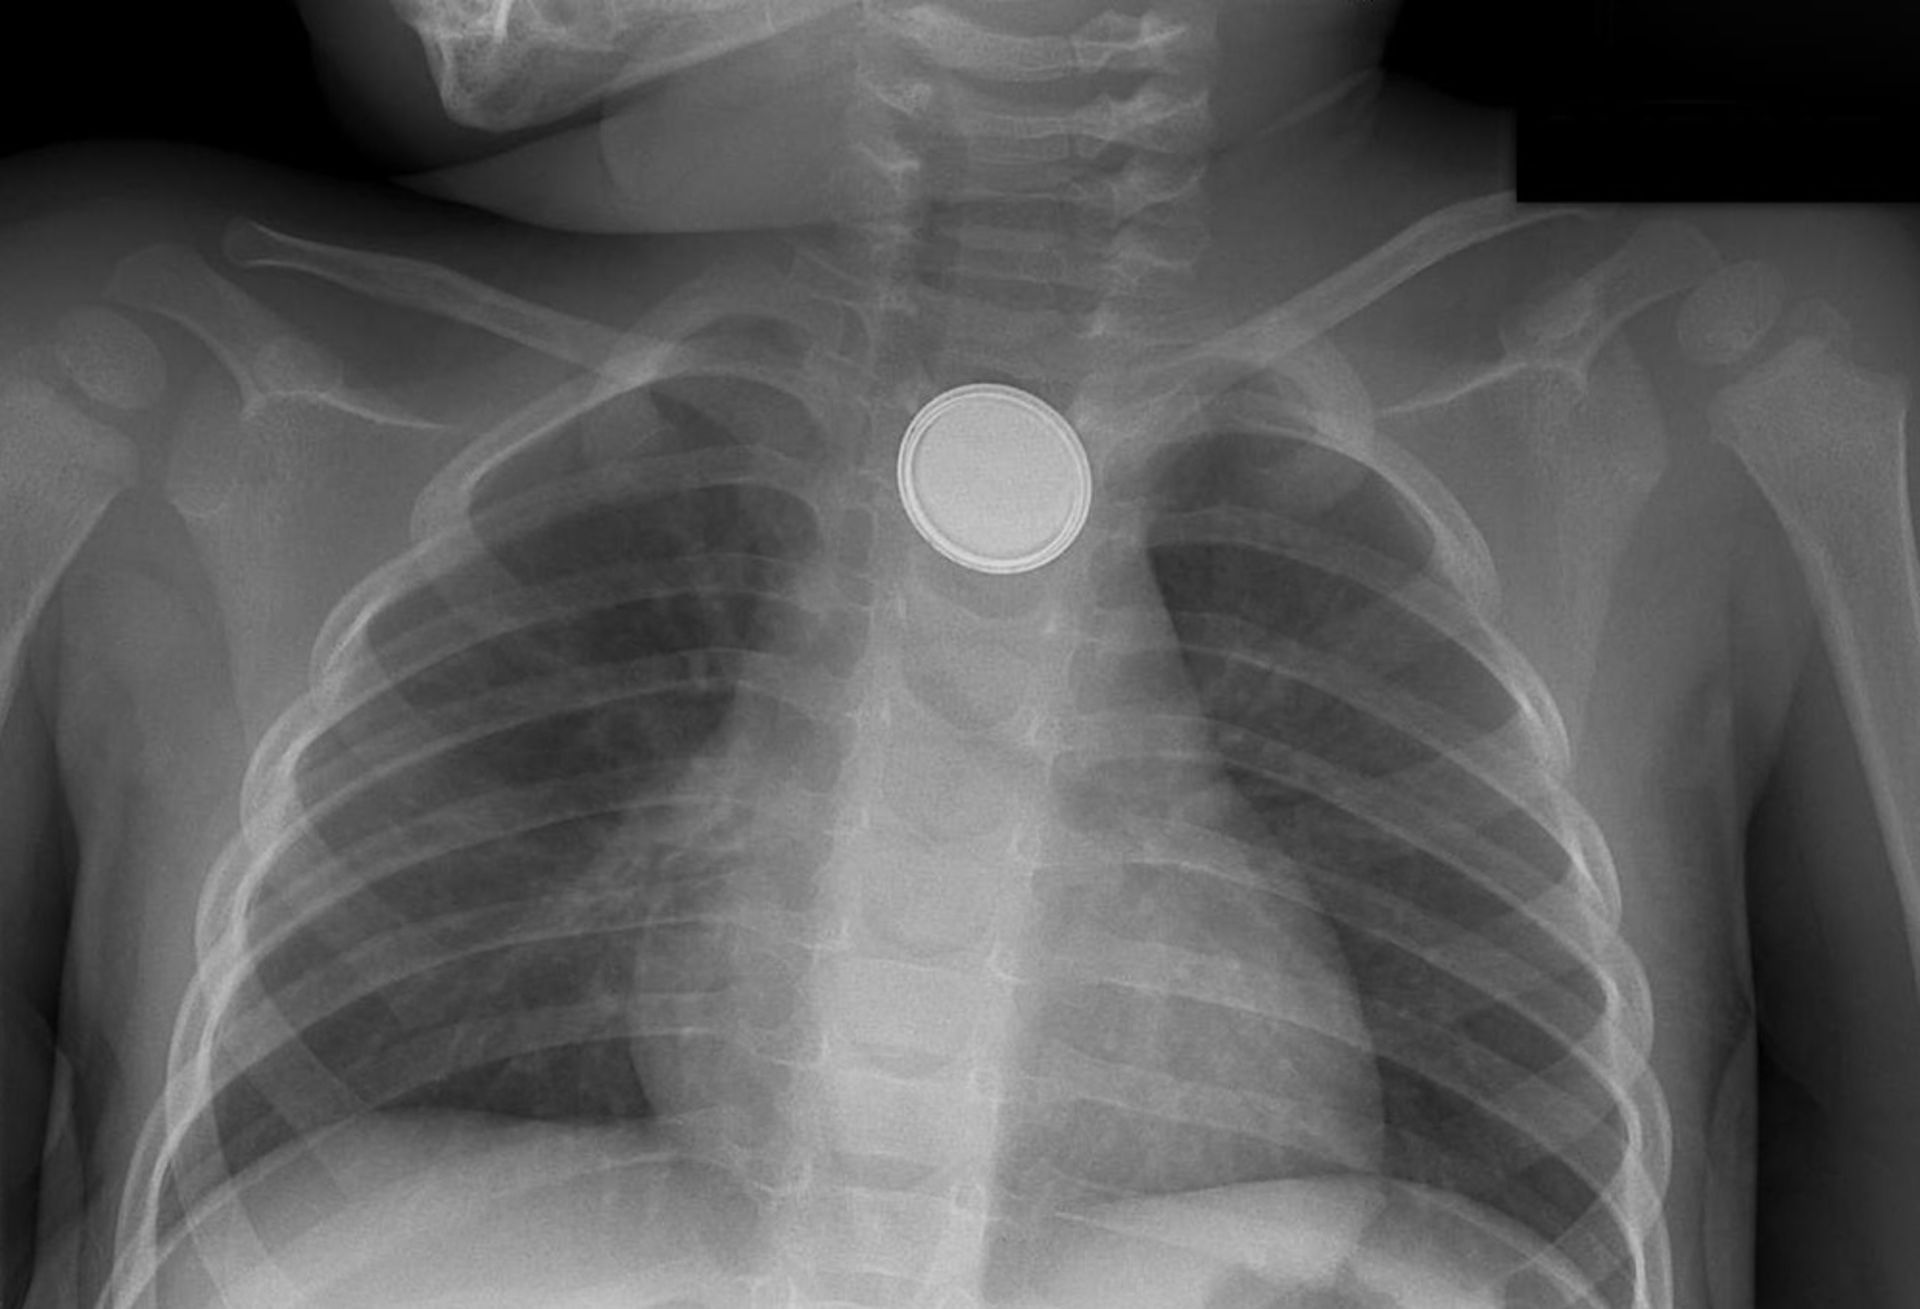

باتری دکمه‌ای

زمانی که باتری در حال گذر کردن از معده است؛ ما هم‌چنان آن را تحت نظر داریم و از والدین می‌خواهیم که ظرف ۲۴ تا ۴۸ ساعت مدفوع بچه را زیر نظر بگیرند و بعدا به شکل زمان‌بندی شده، آن را برای بررسی با پرتو ایکس و اطمینان از گذشتن باتری از لوله گوارش بازگردانند.